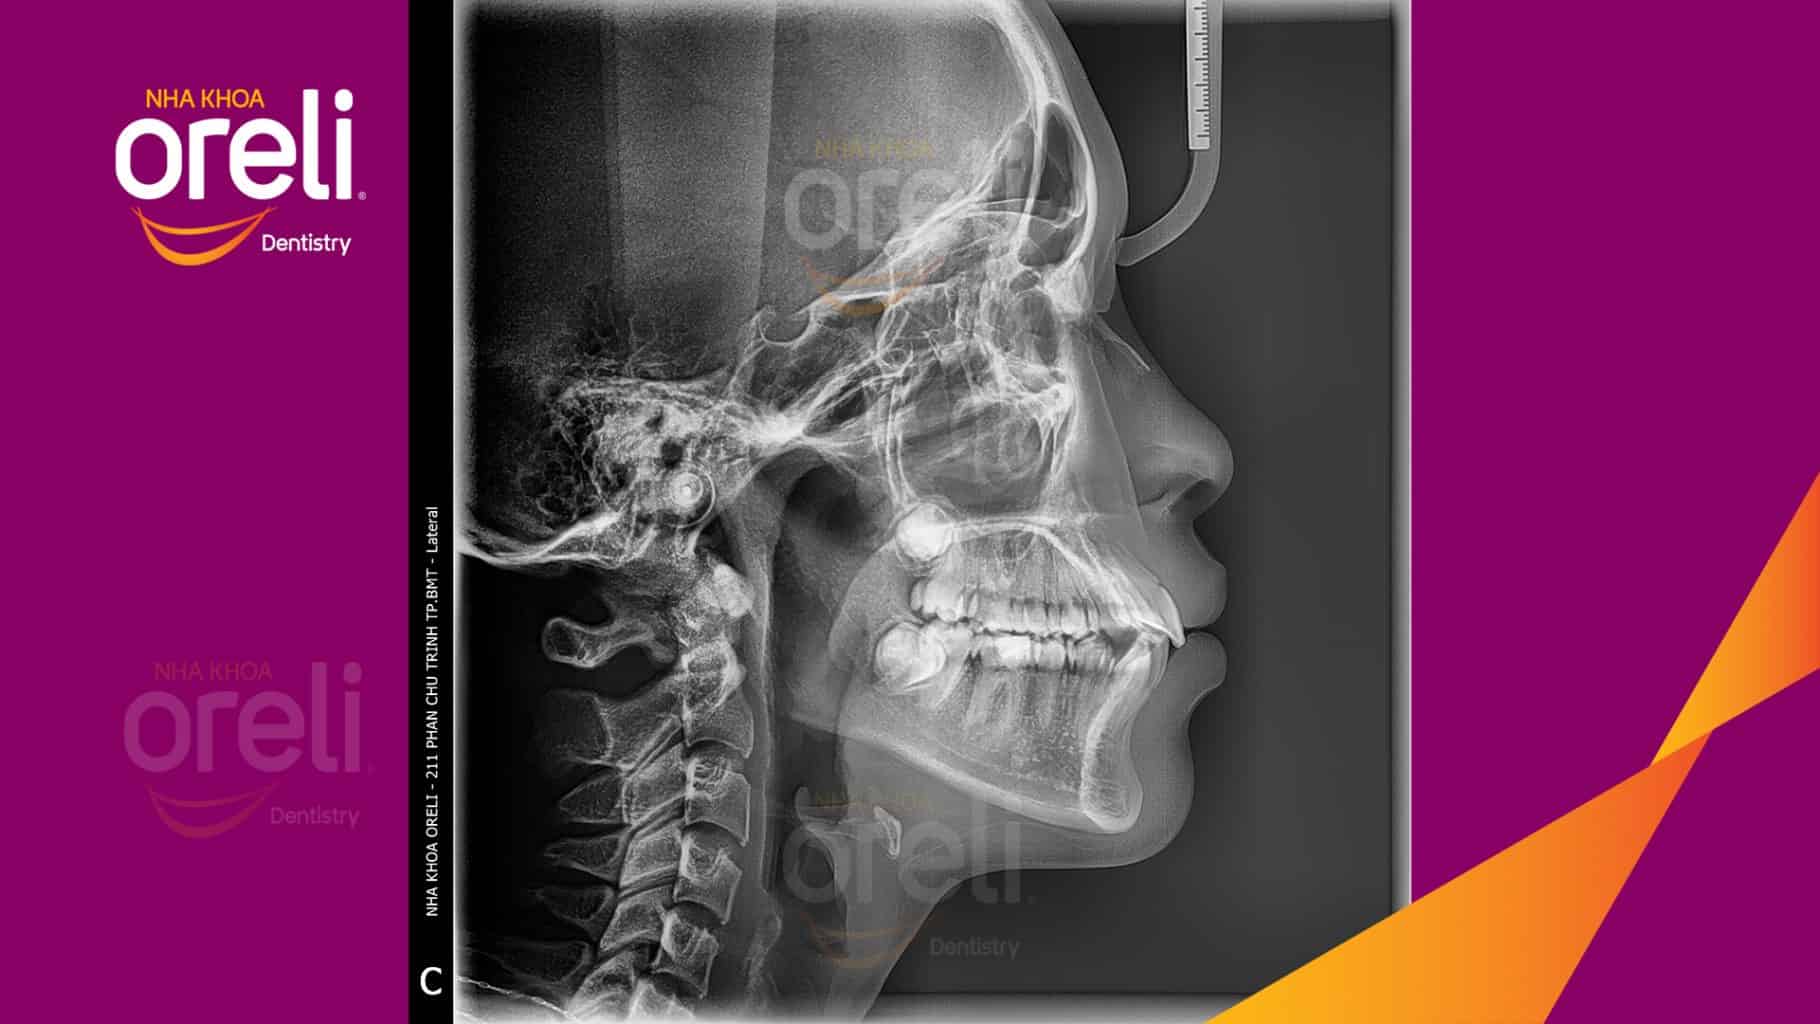

Tình trạng: Nhô xương ổ, trục răng nghiêng trước hai hàm, độ nhô môi nhiều

Giải pháp: Nhổ răng 4 chỉnh hô

Thời gian: 24 tháng

Kết quả: Nụ cười hài hòa, mặt nghiêng đẹp, trục răng cửa đứng